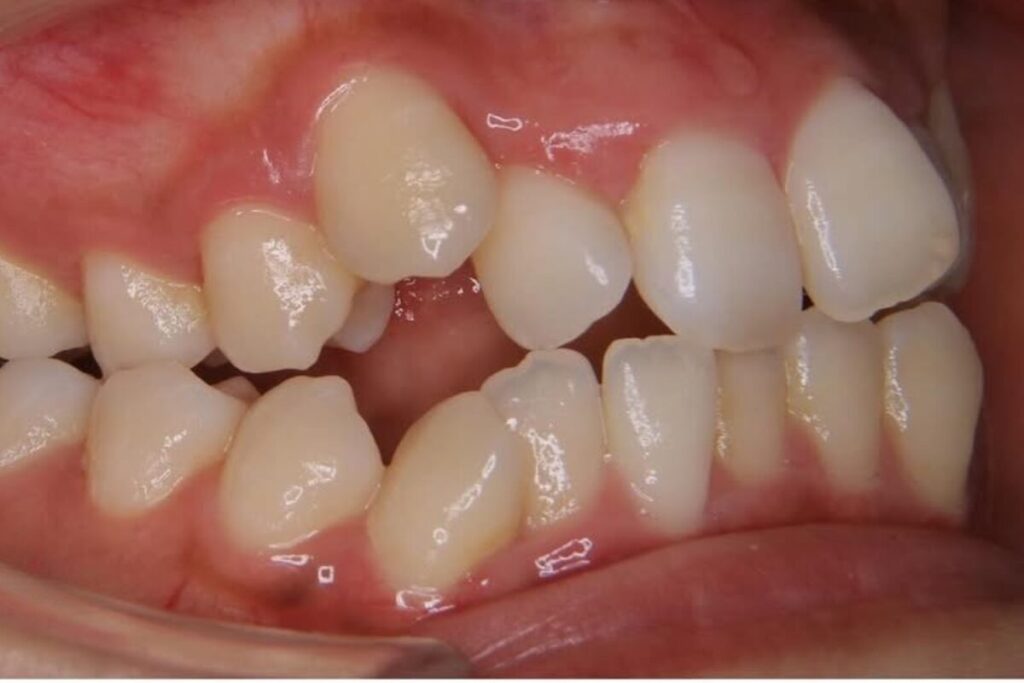

| 患者 | 28歳男性 |

|---|---|

| 主訴 | 歯ならびのガタガタ |

| 診断名 | UR7/LR7クロスバイトと上下叢生を伴うAngleⅠ級sk.1不正咬合 |

| 治療内容 | マウスピース型矯正装置(インビザライン)、部分的に上顎前歯部にワイヤー併用 |

| 抜歯の有無 | 非抜歯 |

| 治療期間 | 2年 |

| 費用(税込) | 594,000円 |

| リスクと副作用 | 痛み等、歯根吸収/歯肉退縮、後戻り、むし歯・歯肉炎の可能性。 |

【医師コメント】

上下のガタつきで来院された患者さんです。

精密検査の結果、UR7/LR7のクロスバイト(交叉咬合)と上下の叢生を伴う AngleⅠ級(sk.1)不正咬合 と診断しました。奥歯の前後関係はⅠ級で大きなズレは強くない一方、奥歯の噛み合わせのズレとスペース不足が原因でした。

治療はインビザラインを主体に非抜歯で計画し、歯列全体のバランスとかみ合わせの安定を意識しながら段階的に改善を進めました。

終盤、UL2のローテーションがわずかに残ったため、仕上げの精度を高める目的で上顎前歯部に部分的にワイヤーを併用しています。

治療は計画に沿って進行し、2年で歯列の配列とかみ合わせの改善を図ることができました。